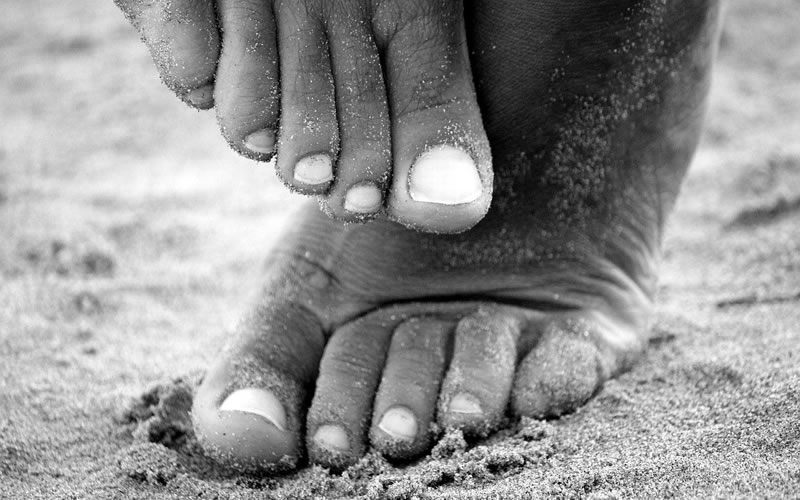

Patologías y trauma

Cirugía del Hallux Valgus, Dedos en Martillo.

Cirugía Mínimamente Invasiva de Antepié.

Cirugía del Hallux Valgus, Dedos en Martillo.

Cirugía Mínimamente Invasiva de Antepié.

Especializada en Cirugía reconstructiva ortopédica y traumatológica de Pie y Tobillo.